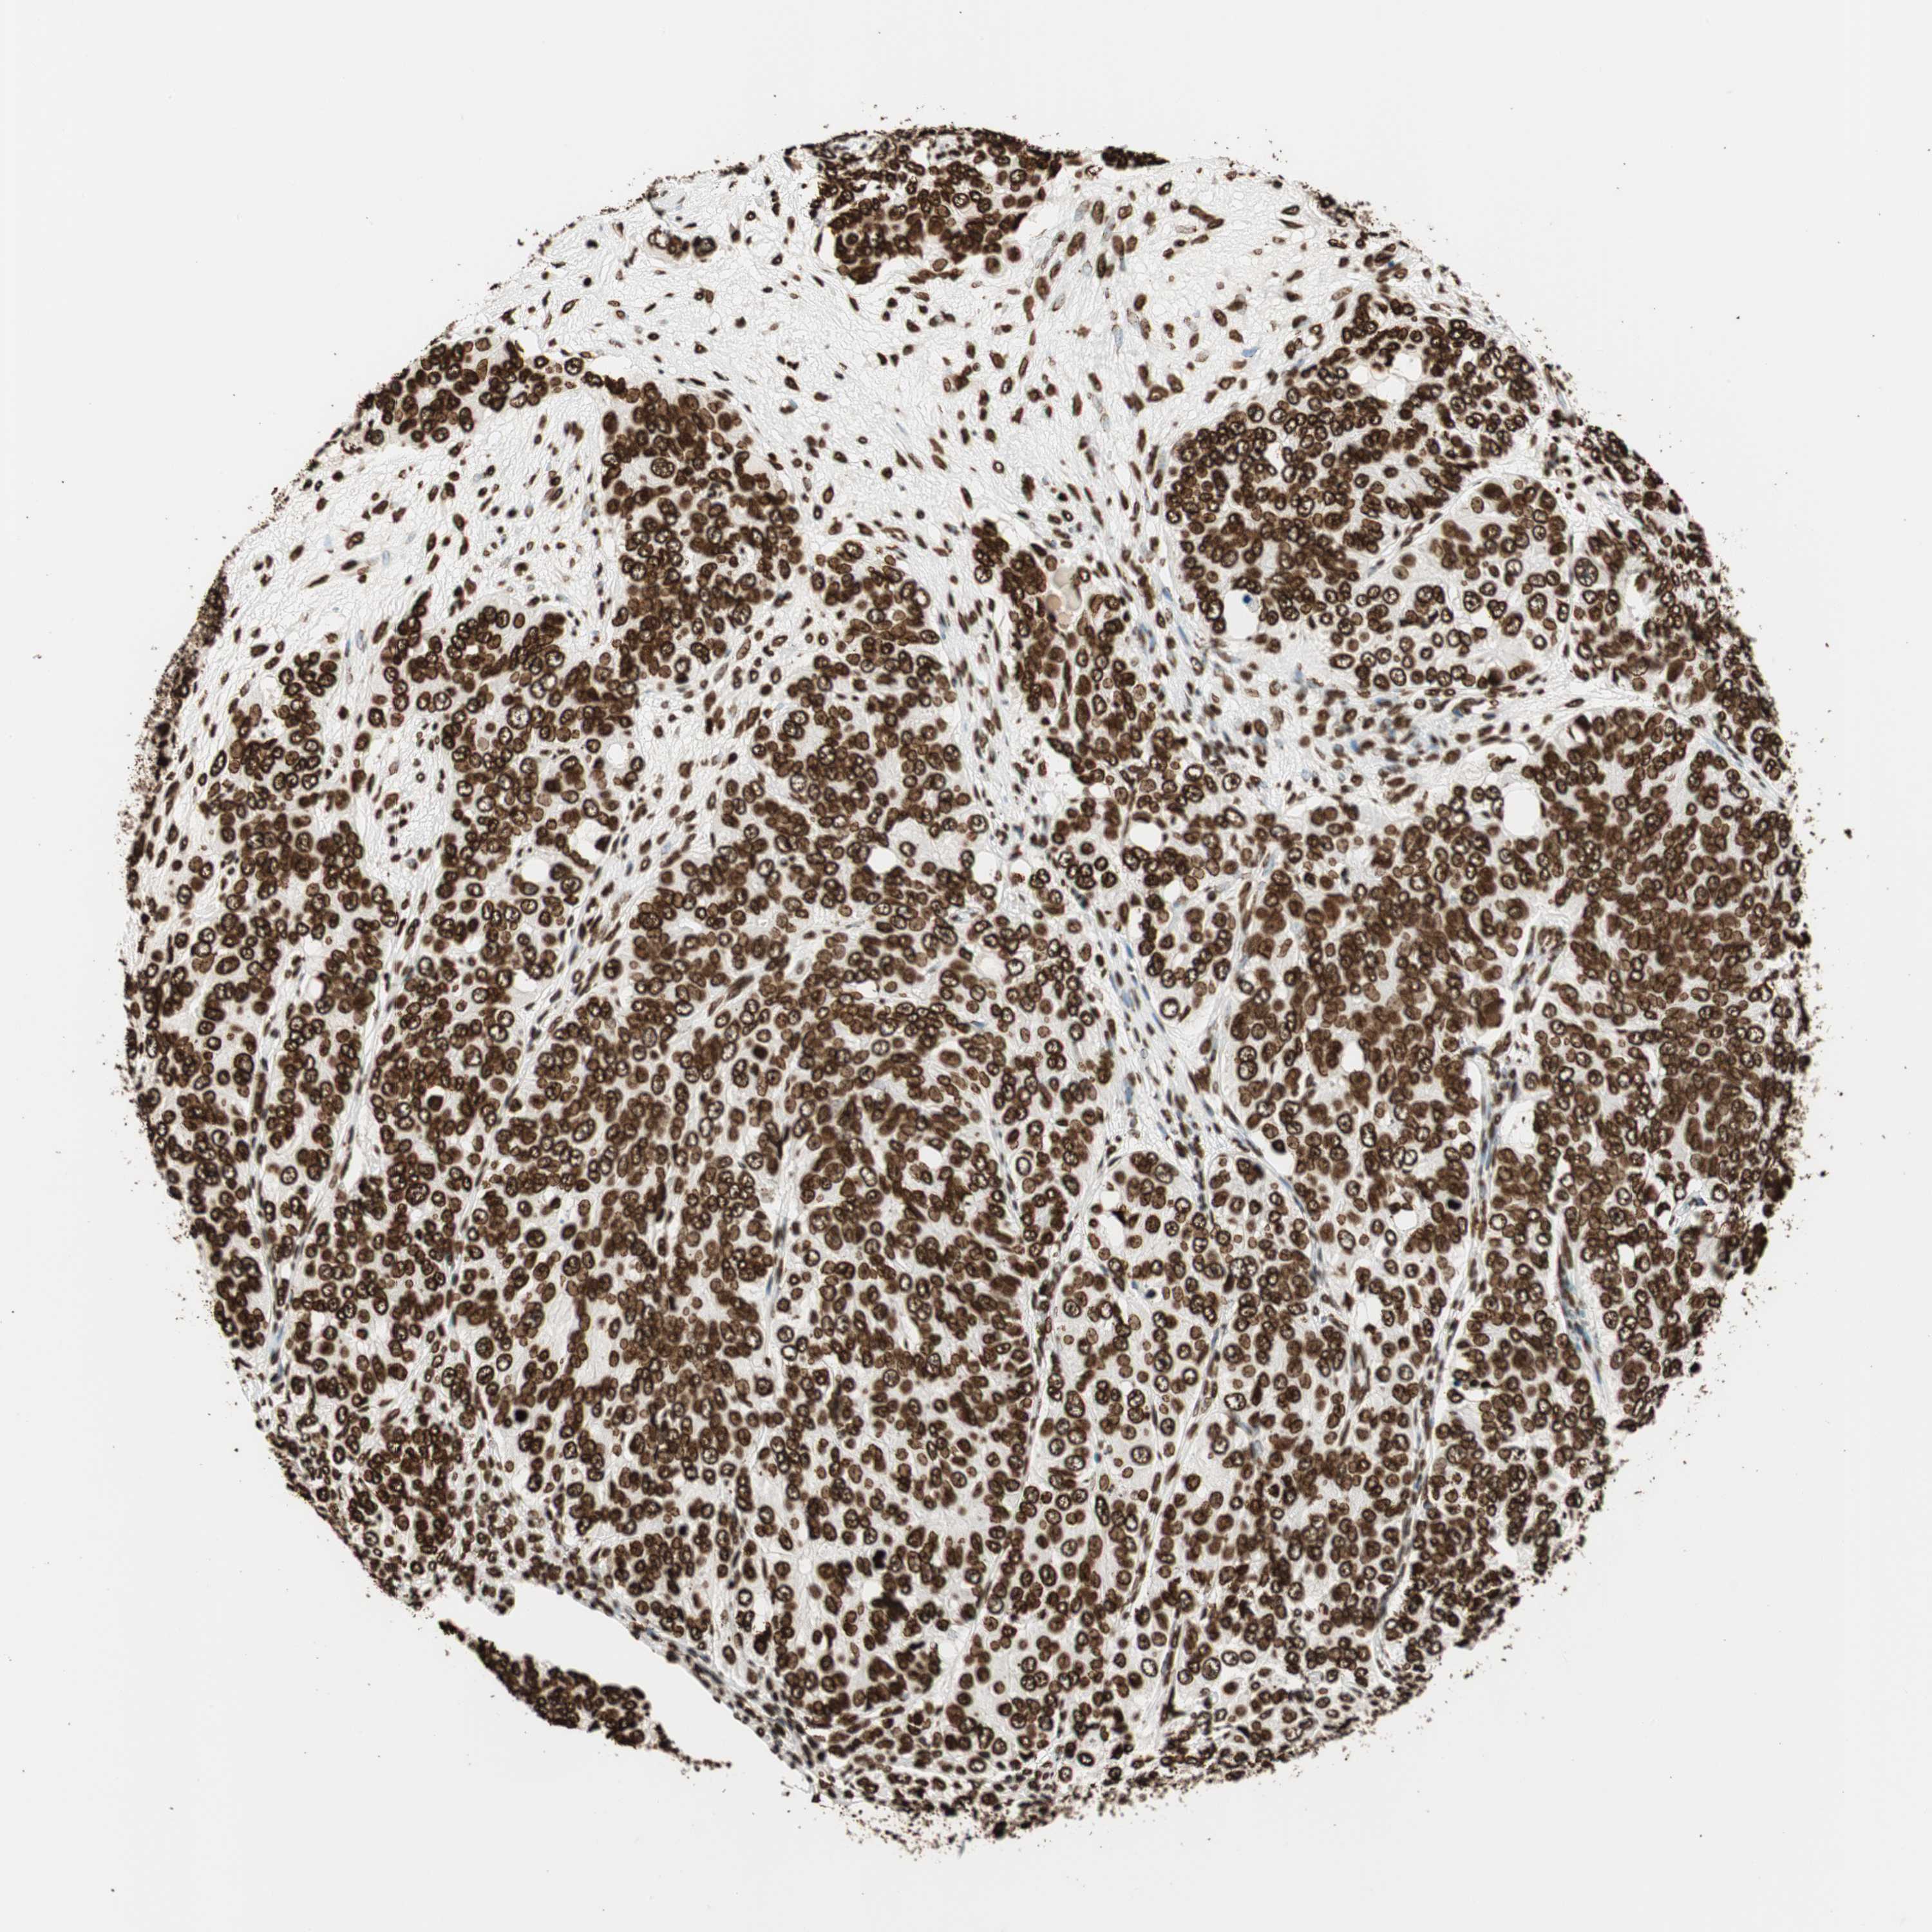

OVARIAN CANCER - Protein expressioni

A mouse-over function shows sample information and annotation data. Click on an image to view it in a full screen mode. Samples can be filtered based on level of antibody staining by selecting one or several of the following categories: high, medium, low and not detected. The assay and annotation is described here.

Note that samples used for immunohistochemistry by the Human Protein Atlas do not correspond to samples in the TCGA dataset.

Antibody stainingi

Antibody staining in the annotated cell types in the current human tissue is reported as not detected, low, medium, or high, based on conventional immunohistochemistry profiling in selected tissues. This score is based on the combination of the staining intensity and fraction of stained cells.

Each image is clickable and will lead to virtual microscopy that enables deeper exploration of all samples and also displays staining intensity scores, fraction scores and subcellular localization as well as patient and tissue information for each sample.

Antibody CAB008558

Staining

High

Medium

Low

Not detected

Intensity

Strong

Moderate

Weak

Negative

Quantity

>75%

75%-25%

<25%

None

Location

Nuclear

Cytoplasmic/membranous

Cytoplasmic/membranous,nuclear

Cystadenocarcinoma, serous, NOS

Carcinoma, endometroid

Cystadenocarcinoma, mucinous, NOS

Carcinoma, NOS